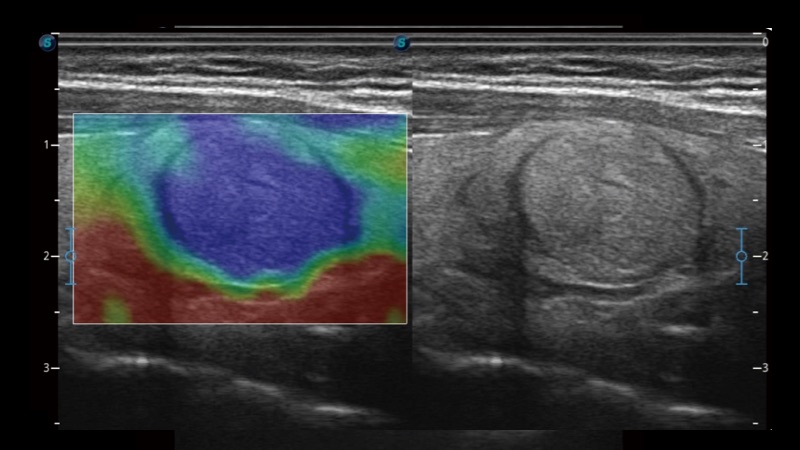

腔内探头

凭借狗万官方网站先进的成像技术和优异的探头技术提供的清晰的图像表现,您可以更自信地做出临床决策。